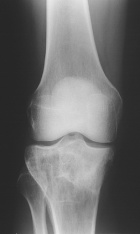

Case 8

M.L. - 44 year old female presents with seven month hx of right knee pain.

Zoom image: Radiological image Radiological image.